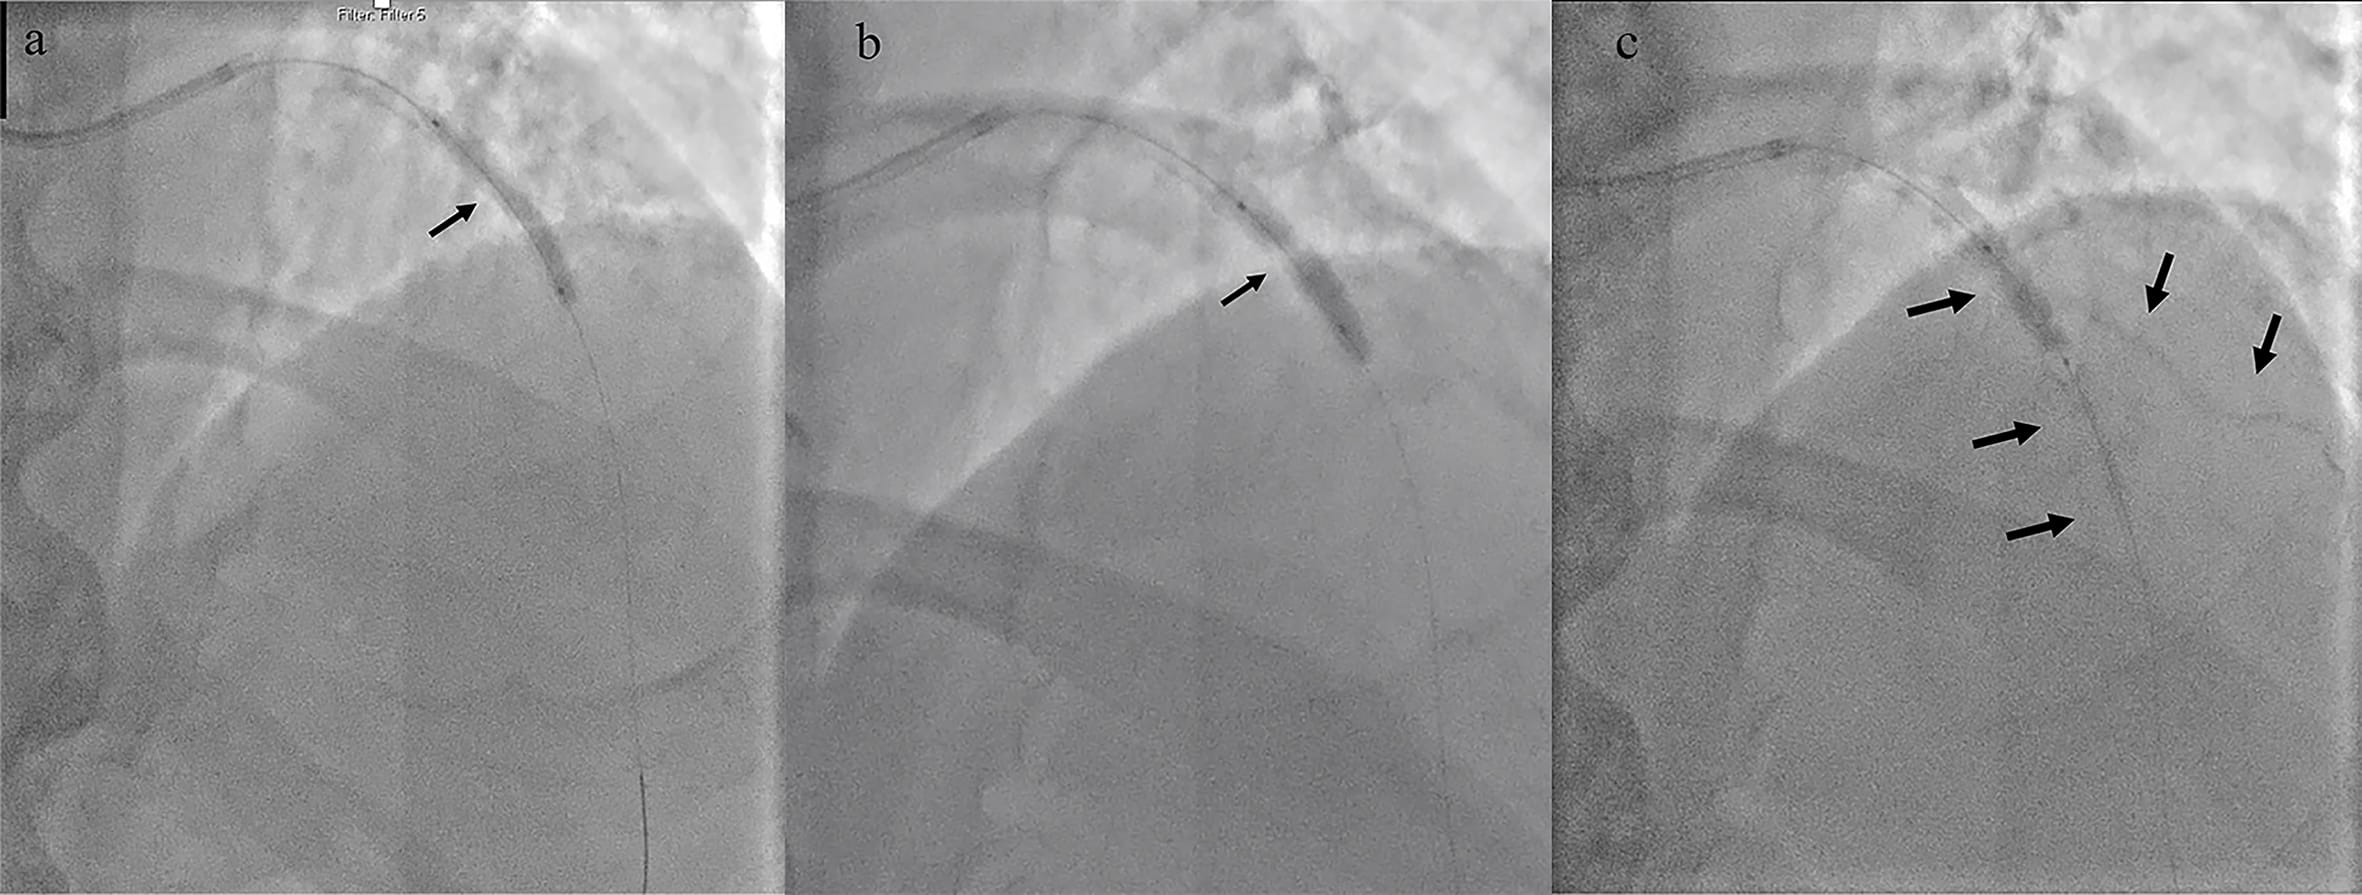

resulted in bursting of a 3.5 mm non-compliant balloon (Fig. 3). Intravascular

imaging visualised concentric calcium (Fig. 4). Subsequently, we used a 3.5 mm

Fig. 3.IVUS exhibiting concentric calcification at the site of lesion, which was not yielding. (a) Calcium arc extending from 9’o clock to 5’o clock positions (shown by the arrows). (b) Calcium arc extending from 1’o clock to 6’o clock positions (shown by the arrows).